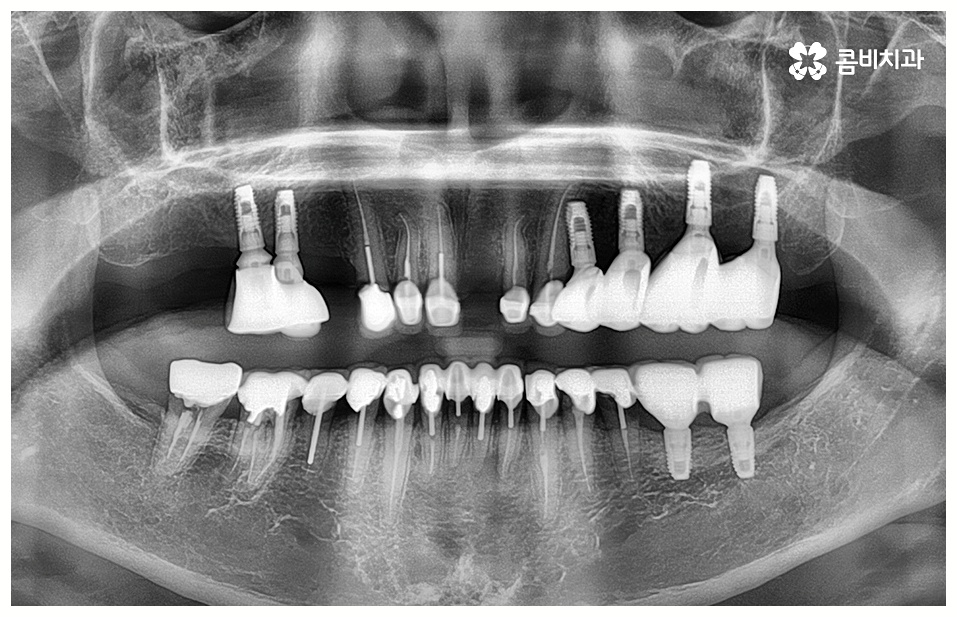

임플란트 치료는 자신의 자연 치아를 대신해 오랫동안 쓸 수 있도록 장기적인 안정성을 추구하는 것이 중요하기 때문에 최초의 진단과 치료 계획을 꼼꼼하게 세우는 것이 필수라고 할 수 있어요.

또한 풍부한 임상 경험과 노하우를 가진 숙련된 의료진, 다각적이고 체계적인 분석을 할 수 있는 3D CT 와 같은 정밀 분석 장비를 갖추고 보다 안정성이 검증된 정품 재료의 사용 여부 등을 잘 체크해야 할 거예요.

임플란트 수명은 개인차가 있겠지만 잇몸 케어 등 사후 관리 역시 철저하게 해 주신다면 반영구적인 사용도 가능한 만큼 치과에서 알려드리는 주의 사항을 잘 따라주시고 검진 및 스케일링 등에 신경 쓰시고 꾸준히 믿고 찾을 치과를 잘 선택해야 할 수 있어요.